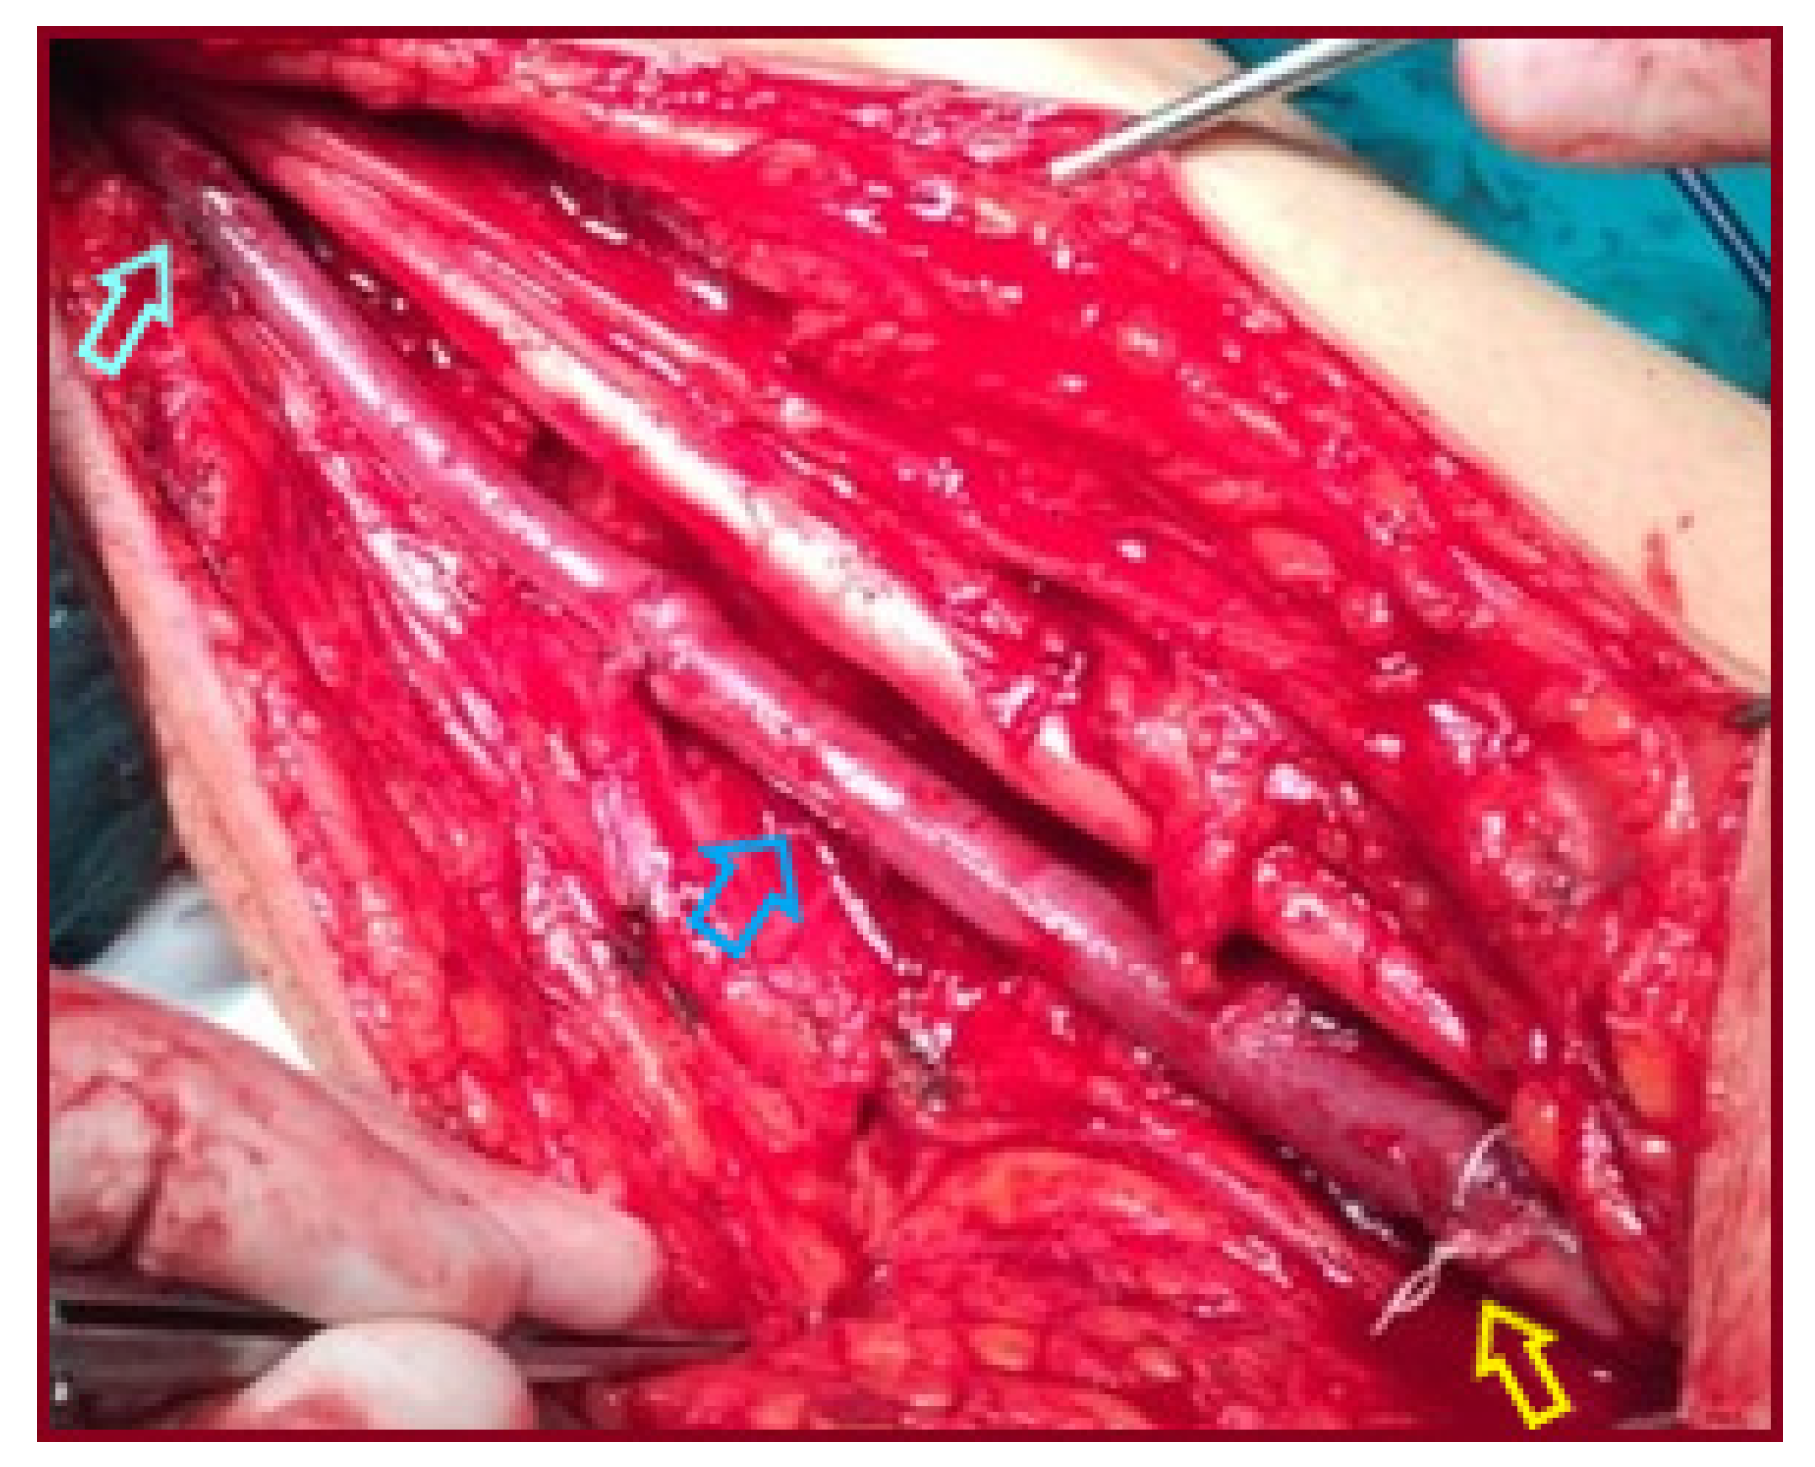

| 1/ 2001 | 28/M | No/ Palpable mass | R/Distal third of BA, extending to ulnar artery | 3.5 | Aneurysm excision & reversed BV interposition between BA & RA, UA ligation | NA |

| 2/ 2007 | 46/M | No/ Palpable mass | L/ Distal half of BA | 4 | Aneurysm excision & reversed BV interposition | NA |

| 3/ 2015 | 65/M | No/ Palpable mass | L/ Two proximal thirds of BA | 4 | Aneurysm excision & reversed BV interposition | NA |